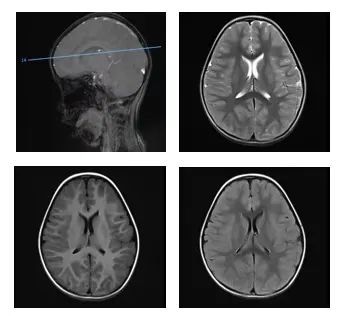

晓月在补液治疗时,渐渐出现嗜睡、意识模糊、双眼上翻凝视等症状,最后竟然陷入昏迷!紧急抢救后,她被送入重症监护室(PICU)。检查发现,她急性酒精中毒,出现了严重代谢性酸中毒、大脑功能受损。

检查发现,患儿出现了颅内多发病变